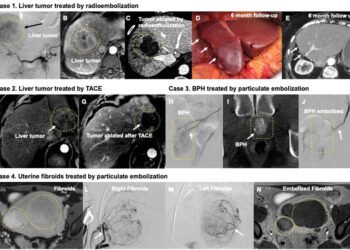

Radioembolization, also known as Y-90 radioembolization, is a minimally invasive procedure that involves the injection of tiny microspheres into the artery...